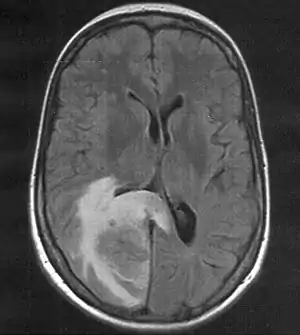

| MRI (T2 flair) showing a brain metastasis with surrouding edema | |